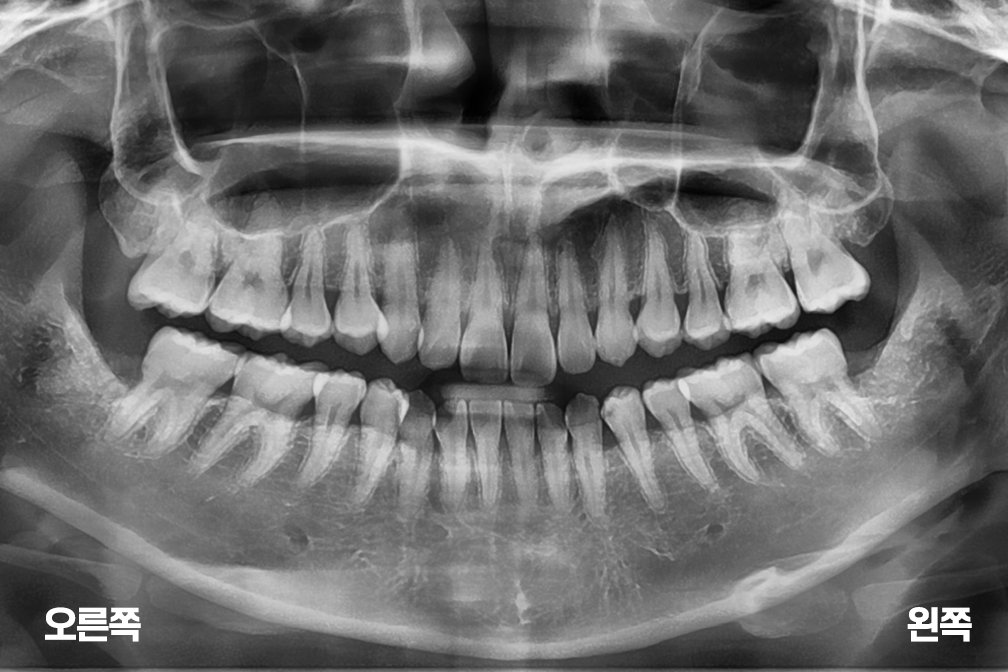

사랑니발치 아래 양쪽 사랑니 발치

사랑니 발치

위 전후사진은 이미지사진으로 실제 눈으로 보는 것과는 다를 수 있으며, 환자의 치아상태과 방법에 따라 치료결과가 다를수 있습니다.